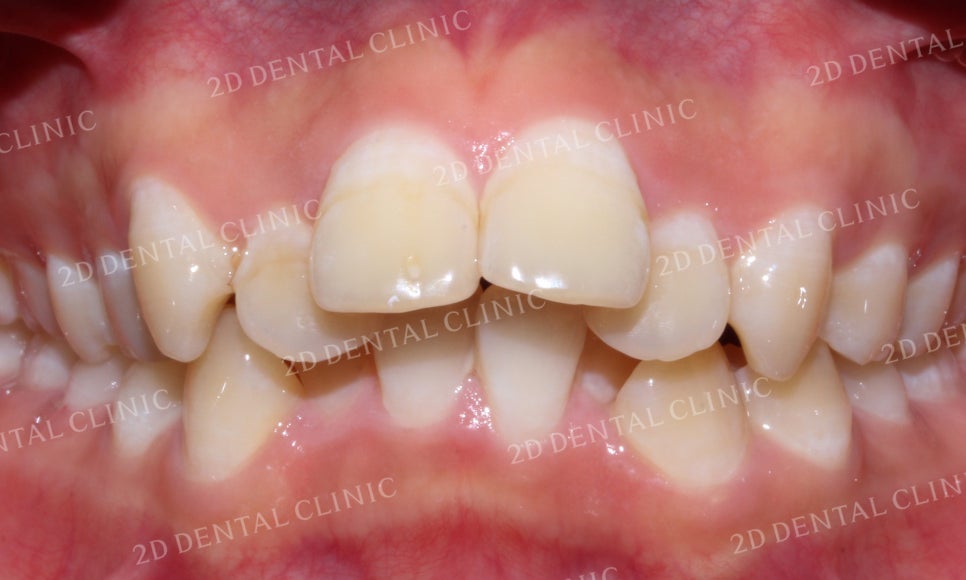

"돌출앞니 교정 전"

돌출앞니 전체교정 전

미소 시 전치부의 치아들을 보시면

전치부의 각도가 과도하게 뻐드러져 있고

중절치가 돌출된 상태입니다.

또한 전체적인 치열이 총생으로 인해

삐뚤삐뚤하게 배열된 상태입니다.